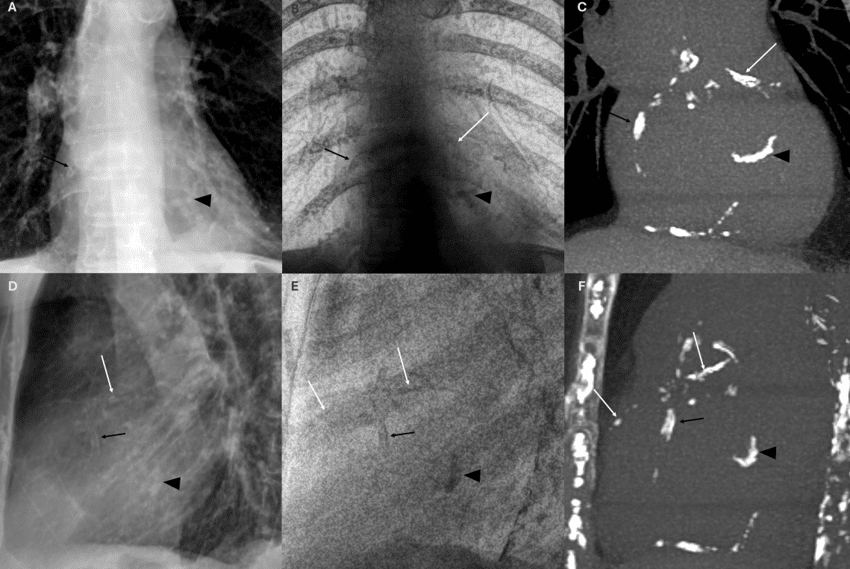

Coronary artery calcium becomes visible in the SpectralDR bone image and is confirmed on CT.

SpectralDR bone images emphasize skeletal structures, allowing clearer visualization of the fracture compared with the conventional radiograph.